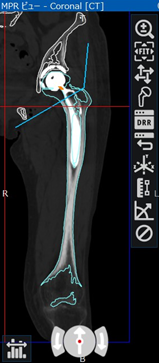

- 術前CTデータをZedHipに取り込む

- 寛骨臼側: 原臼位にセメントレスカップをプレスフィット

- 大腿側: セメントレスステムを近位大腿骨軸に平行に挿入

Stem Anteversion (SA): 15度基準面:retrocondylar plane

* SA: ネックと後顆接線となす角をXY平面に投影 -

ただし、Combined anteversion (CA) theoryに準じRAとSAを症例により調整

CA: 30~50度を目標

- ROM simを施行しI-I impがないことを確認して終了

- 術後1週のCTデータをZedHipに取り込む

- 術後評価機能を用いて設置角度評価

RI, RA, SA

- 術前計画機能を用いて再度術後ROM simを施行

計測肢位: ①屈曲120度②屈曲90内転20内旋30度③内転10外旋30度④伸展30度インピンジメント: 角度 (①と④で最大値を評価)様式 インプラント同士: I-I impインプラントと骨: B-I imp骨と骨: B-B imp